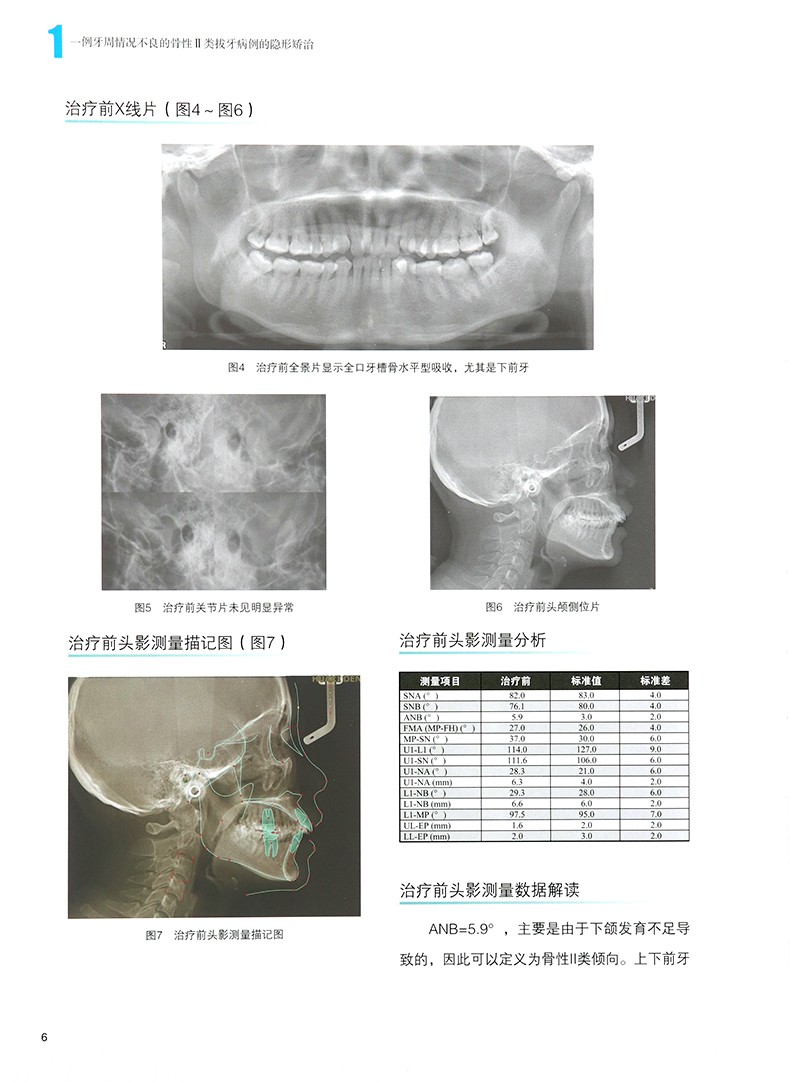

【無托槽隱形矯治科技病例薈萃】

內容簡介

無托槽隱形矯治科技問世以來,憑藉其美觀性、舒適性、方便性以及矯治療程的可視性等優點,深受醫生和患者的喜愛。 無托槽隱形矯治器的市場需求量正在大幅度增加,無托槽隱形矯治的適應證也在不斷擴大,越來越多複雜的病例可以通過無托槽隱形矯治器取得滿意的治療目標。

2020年,愛齊公司面向全國各地徵集200個不同類型的病例,最終入選了60個優秀病例,其中大部分來自公立醫院,彙集成這本《無托槽隱形矯治技術病例薈萃》。 包含青少年、安氏|類、安氏Ⅱ類、

安氏川類、正畸-正頜聯合治療,全方面地展示了我們在臨床中會遇到的常見病例,不僅展示了每個

病例完善的診斷和治療設計,還涵蓋了臨床中常見問題及處理方法。